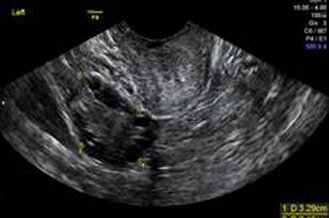

正常卵巢

卵巢巧克力囊腫